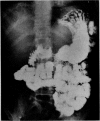

Images in this article